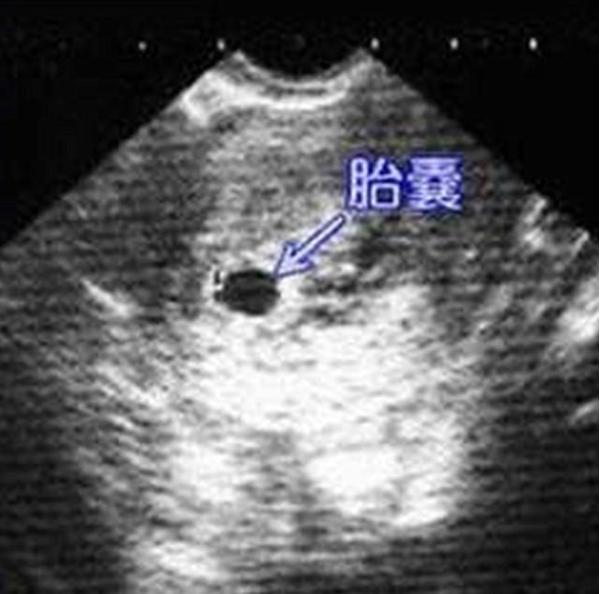

胎囊也叫孕囊或者妊娠囊,是胚胎最初的形态,将来宝宝就从这里长出来。 胎囊形成时间:孕30~40天。 一般月经比较正常的女性,停经35天 (孕5周)左右,通过B超就可以看到胎囊;孕6周时,孕囊的检出率为100%。 胎囊大小与孕周是相对应的,医生通常是通过B超检查的 孕囊大小 来推算孕周,这要比根据末次月经时间推算要准确。 1、异常胎囊 位置异常: 健康的胎囊应该在 卵黄囊内径一般在 35 mm,妊娠第 510 周逐渐增大,而 10 周之后逐渐减小。 卵黄囊的数量可用以判断多胎妊娠的羊膜囊性。通常来说,胚胎存活时卵黄囊数量与羊膜囊数量一致。因此,单绒单羊妊娠时可表现为 2 个胚胎、1 个绒毛膜囊、1 个羊膜囊和 1 个卵黄囊。孕囊大小对照表 怀孕4周:胎儿0.2厘米,此时的胎儿体积非常的小,用b超是看不到痕迹的。 怀孕5周:胎儿0.4厘米,通过b超可以看见胎囊,也或许可以看到胎芽。 怀孕6周:胎儿0.85厘米,通过b超可以看清楚胎囊,也可以看见胎芽及胎心跳。

孕囊胎儿大小对照表 1、4周:胎儿只有0.2厘米。 受精卵刚完成着床,羊膜腔才形成,体积很小。 超声还看不清妊娠迹象。 2、5周:胎儿长到0.4厘米,进入了胚胎期,羊膜腔扩大,原始心血管出现,可有搏动。 B超 可看见小胎囊,胎囊约占宫腔不到1/4,或可见胎芽。 3、6周:胎儿长到0.85厘米,胎儿头部、脑泡、额面器官、呼吸、消化、神经等器官分化,B超胎囊清晰 3、妊娠23周时HCG为mIU/m1; \n 4、妊娠34周时HCG为mIU/m1; \n 在妊娠4周左右HCG数值一般为隔天翻倍增长, 翻倍好不好也是判断妊娠是否正常4周:胎儿只有0.2厘米。 受精卵刚完成着床,羊膜腔才形成,体积很小。 超声还看不清妊娠迹象。 5周:胎儿长到0.4厘米,进入了胚胎期,羊膜腔扩大,原始心血管出现,可有搏动。 B超可看见小胎囊,胎囊约占宫腔不到1/4,或可见胎芽。 6周:胎儿长到0.85厘米,胎儿头部、脑泡、额面器官、呼吸、消化、神经等器官分化,B超胎囊清晰可见,并见胎芽及胎心跳。 7周

妈妈怀孕的每个周期,孕囊都在不断地发生着变化: \n 4周:妈妈肚子里的胎儿只有02厘米,体积很小,用超声还看不清妊娠迹象。 \n 5周:胎儿长到04厘米,进入了胚胎期,羊膜腔扩大,原始心血管出现。通过B超可看见小胎囊,胎囊约占宫腔不到1/4。 \n 1 问: 胎囊的问题怀孕47周的胎囊应该是多大的 答: 妊娠B超,闭经5周可见胚囊,6周可见胚芽,7周可见胎儿搏动详情>> 2 怀孕60天有胎囊发现没有胎牙,何时胎囊会自己排出;孕囊、胎芽、胎心 孕囊、胎芽、胎心,在孕早期是根据时间顺序出现的。也就是在子宫内先出现孕囊(确定宫内孕),再出现胎芽(确定孕周),最后出现胎心(提示宝宝存活)。 孕囊(孕30—40天) 是怀孕最初胚胎的形态,被羊膜、血管网包裹的小胚胎。